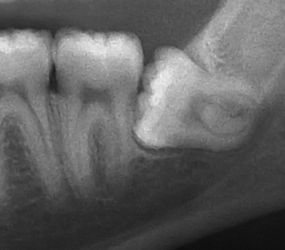

Wisdom teeth usually erupt between the ages of 14 and 30 and can cause extreme discomfort in some people. They can cause the jaw and surrounding gums to feel swollen and uncomfortable. In more extreme situations, they can cause more severe issues such as infection or permanent shifting of the teeth.

At Hullmark Dental we examine your wisdom teeth and depending on the location, direction of eruption and proximity to vital nerves, we may recommend extraction. In very extreme cases we may refer you to an oral surgeon where you would have the option of general anaesthesia to remove your teeth.